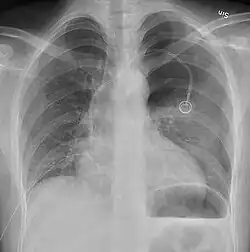

Chest X-ray showing a pneumothorax on the right (left in the image), where the absence of lung markings indicates that there is free air inside the chest -

Chest X-ray showing the features of pneumothorax on the left side of the person (right in image)